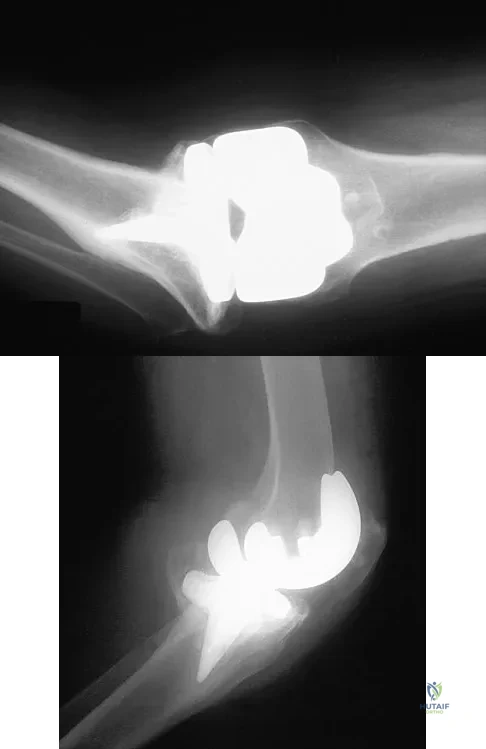

Question 60

A 78-year-old woman falls onto her nondominant left elbow and sustains the injury shown in Figure 5. What treatment option allows her the shortest recovery time and highest likelihood of good function and range of motion?

Explanation